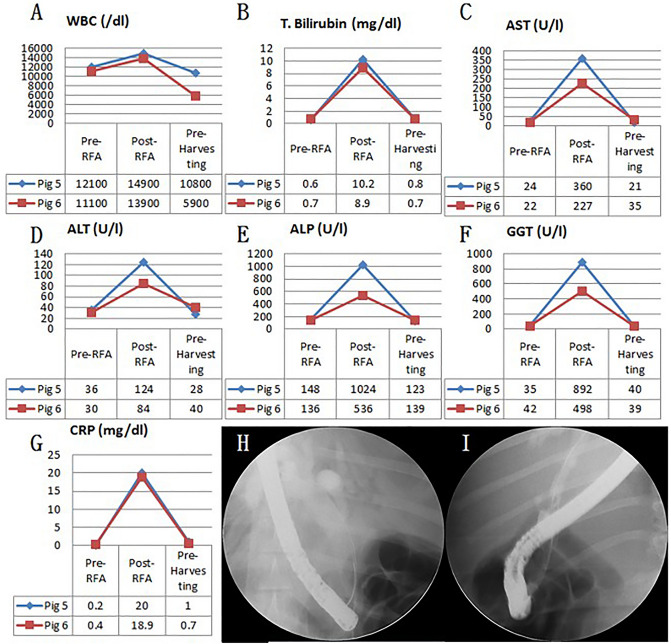

Fluoroscopic analysis via ERCP and blood analysis

In all six swine animal models, we succeeded in generating BSS using intraductal RFA without any complications such as bleeding or perforation (success rate = 100% (6/6), severe complication rate = 0%). Blood levels of WBC, AST, ALT, ALP, GGT, and CRP of all experimental animals were measured before the intraductal RFA procedure, after the intraductal RFA procedure (2 weeks after RFA), and before euthanizing animals (Figs. 1, 2, 3A–G). Blood levels of WBC, AST, ALT, ALP, GGT, and CRP were elevated after the intraductal RFA procedure but decreased after biliary stenting. Figure 1H,I are biliary fluoroscopy findings at 2 weeks after RFA in experimental animals 1 and 2, demonstrating biliary stenosis. The same trend of blood test results as in Fig. 1 was observed in Fig. 2. The difference between Figs. 1 and 2 was that the follow-up was performed at 3 months after biliary stenting in Fig. 2. Biliary stenosis was confirmed by fluoroscopy findings at 2 weeks after RFA in experimental animals 3 and 4 (Fig. 2H,I). Experimental animals 5 and 6 were followed for 5 months after biliary stenting. They showed the same tendency of blood test results (Fig. 3A–G). Biliary stenosis was also confirmed by fluoroscopy findings at 2 weeks after RFA in experimental animals 5 and 6 (Fig. 3H,I).